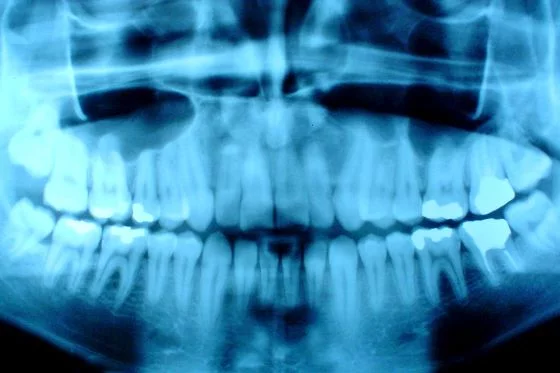

Jak poinformowała rzeczniczka miejskiego szpitala zespolonego w Olsztynie, Daria Rodziewicz, zespół olsztyńskich specjalistów pod kierunkiem dr Anny Bromirskiej–Małyszko musi odciąć żuchwę zrośniętą z podstawą czaszki i z podstawą kości skroniowej, a następnie wstawić implanty czyli sztuczne stawy, aby przywrócić sprawność chłopcu.

Operując ją lekarze wprowadzili nowoczesne metody oraz najwyższej klasy urządzenia medyczne. Najpierw na podstawie tomografii komputerowej wykonano model stereolitograficzny szczęk, na podstawie którego zaplanowana została operacja. Specjaliści w ten sposób sprawdzili, jak zestawić kości, aby pacjent miał prawidłowy zgryz. Podczas zabiegu zespół operacyjny miał do dyspozycji neuromonitor służący do identyfikacji gałązek nerwu twarzowego oraz piezoelektryczne urządzenie do cięcia kości tzw. piezosurgery – nóż, który pozwolił na selektywne cięcie tkanek twardych bez ryzyka uszkodzenia tkanek miękkich.